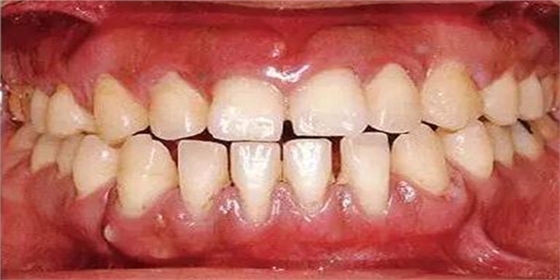

●33歲男性 侵襲性牙周炎廣泛型口腔內(nèi)照片

33歲男性,吸煙(1天10根,12年吸煙史)。菌斑控制狀況不好,牙周探診全頜牙周袋深5~10mm之外,全頜性牙周袋出血,部分牙周袋有排膿現(xiàn)象。X片可觀察到全頜性重度骨吸收。通過(guò)以上檢查可診斷出該患者為侵襲性牙周炎廣泛型。視診可知牙齦雖然有炎癥,但沒(méi)有出現(xiàn)嚴(yán)重浮腫,沒(méi)有大量牙結(jié)石沉積。